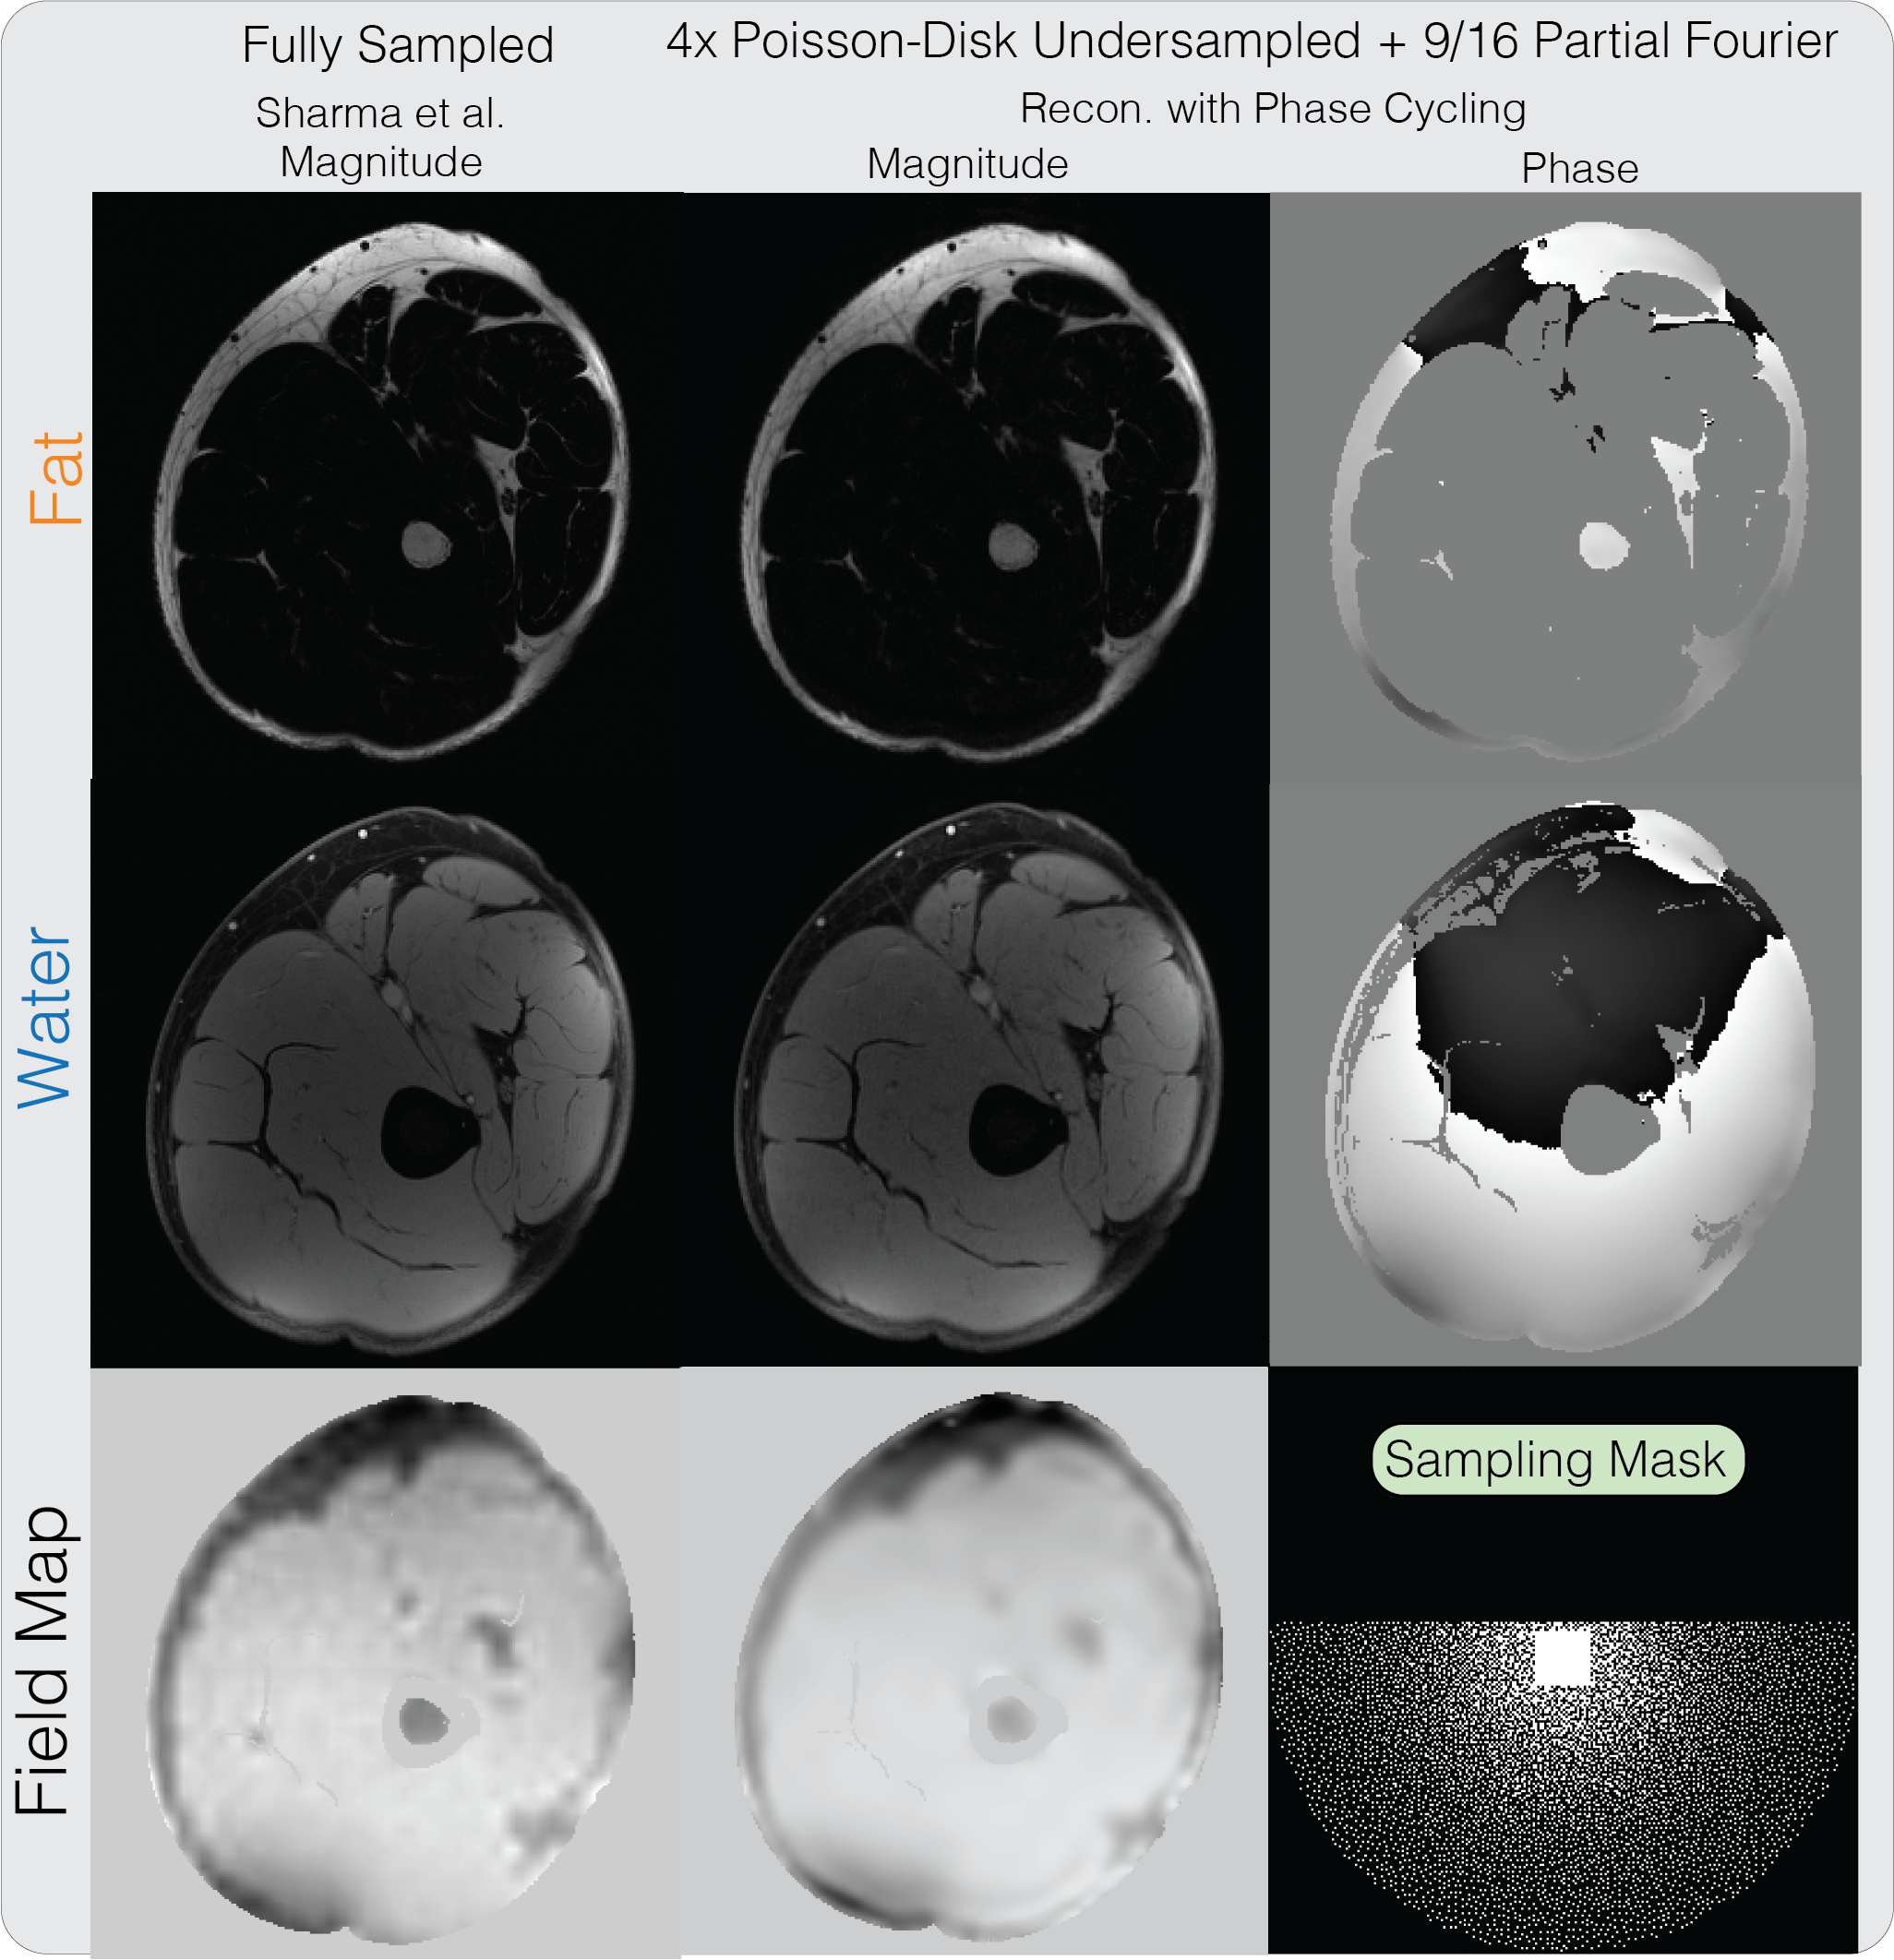

An axial slice of the thigh dataset from the ISMRM Water-Fat workshop toolbox was also used, with the same parameters. The dataset was retrospectively under-sampled by 4 with a variable density Poisson Disk sampling pattern and an additional 9/16 partial Fourier factor. Our proposed method was applied and compared with the result of applying the algorithm of Sharma et al. on the fully-sampled dataset. An regularization on the Daubechies-4 wavelet transform of the image phase was applied.

Figure 7 shows the water-fat reconstruction results on the thigh dataset, combined with partial Fourier, PI and CS. Our proposed method produces similar water and fat images on a partial Fourier dataset, as the fully-sampled reconstruction using the method of Sharma et al. [9]. This demonstrates the feasibility of performing joint partial Fourier and water fat image reconstruction along with PI and CS using the proposed method. One instance of our Matlab implementation of the proposed method took 8 minutes and 23 seconds.

7.

Water-fat + partial Fourier + PI + CS reconstruction result on a thigh dataset. Our proposed method produces similar water and fat images on a undersampled partial Fourier dataset compared to the fully-sampled reconstruction using the method from Sharma et al.